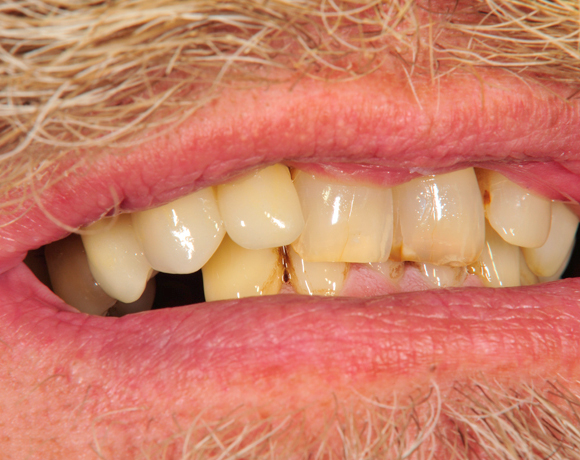

Vollkeramische Implantatkronen aus e.max lassen sich jederzeit mit vollkeramischen Kronen auf natürlichen Zähnen kombinieren ohne, dass ein Unterschied zu natürlichen Zähnen erkennbar ist.

Bei diesem Patienten wurde der nichterhaltungswürdige Zahn 12 mit einem Zerameximplantat versorgt. Nach der Einheilphase wurden auch die Zähne 14 und 13 mit e.max Kronen versorgt